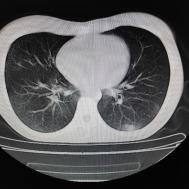

性别:女,年龄:26岁,低热,轻微胸痛,支原体阳性

[影像描述]

两肺内及胸膜下多发斑片状高密度影,部分病灶密度较淡,部分实变,边缘可见渗出改变。

支原体肺炎

支原体肺炎是由支原体引起的以间质改变为主的肺炎。实验室检查支原体抗体呈阳性。支原体侵入肺内可引起支气管、细支气管黏膜及其周围间质充血、水肿,多核细胞浸润,侵入肺泡可产生肺泡浆液性渗出性炎症。CT早期主要改变为肺间质炎症,病变区肺纹理增粗而模糊,病变范围广泛,常累及多个肺叶,单侧或双侧的磨玻璃影及实变影,以双肺下叶多见,多呈小叶性分布。同时,患者的临床症状与CT改变不匹配,即临床症状明显好转或消失但肺部阴影吸收不明显。鉴别诊断:支气管肺炎好发于两中下肺的内、中带,病灶沿支气管分布,呈多发散在小的斑片状影,常合并阻塞性小叶性肺气肿或小叶性肺不张,结合临床多见于婴幼儿或年老体弱者。渗出浸润为主的继发性肺结核病灶表现为结节状或呈不规则斑片状影,边缘较模糊,密度不均匀,病灶内可见小空洞。增殖性病灶密度较高,边缘清楚,病灶内或周围可见不规则钙化灶。浸润性病变常与纤维化并存,可伴有邻近支气管扩张。结核分枝杆菌检查阳性。